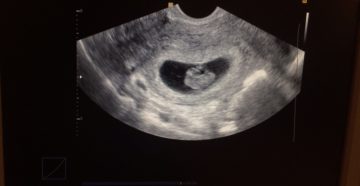

Узи на 8-й неделе беременности и показания к его выполнению Современная медицина обладает множеством средств…

8 неделя беременности – что происходит С эмбриональной точки зрения этот период считается только шестой…